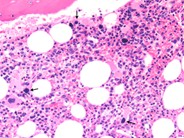

Idiopathic Thrombocytopenic Purpura - 2. Idiopathic Thrombocytopenic Purpura - 4. Immune Thrombocytopenia (ITP): Background, Pathophysiology, Etiology Giant thrombocyte in peripheral blood smear of an ITP patient ... Idiopathic Thrombocytopenic Purpura Smear